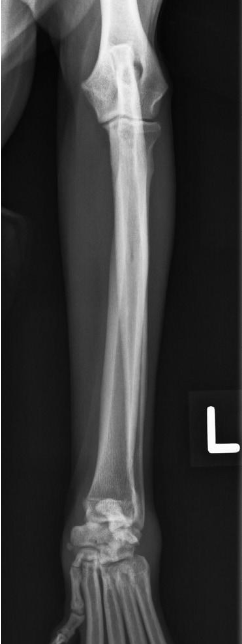

what position do we put the animal in for a cranio-caudal view of the radius and ulna?

sternal recumbency with forelegs fully extended cranially and head elevated away from limb

what radiograph view of the radius and ulna is shown?

cranio-caudal view